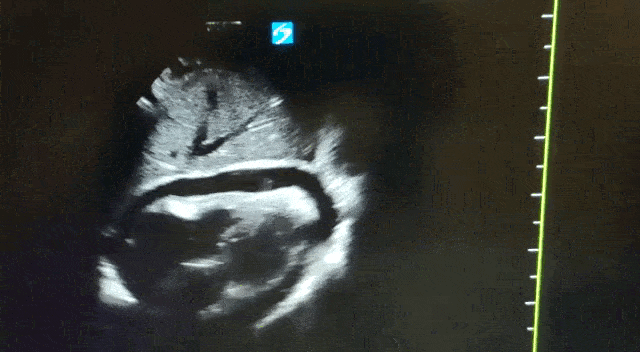

Ce guide qui décrit, clichés et schémas à l’appui, 25 examens POCUS – cardio- thoraciques, abdominaux, urogénitaux, vasculaires, cutanés, tête et cou, musculo-squelettiques – a été conçu pour vous aider à retrouver certaines images cibles, chez l’adulte principalement mais aussi chez l’enfant.

Les indications du Point-Of-Care UltraSound (POCUS) en médecine de premier recours ou médecine d'urgence sont nombreuses. Cette technique s'intègre dans une démarche clinique et doit répondre à une question dont la réponse est binaire. La miniaturisation, l'ultraportabilité, les immenses progrès technologiques réalisés permettent désormais de réaliser des examens au chevet des patients (Bedside US), et cela quel que soit l'endroit où ils se trouvent.